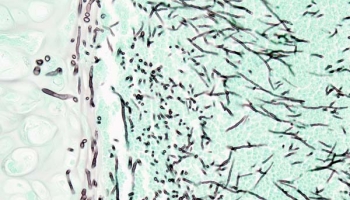

- 잠잠하다 했더니...'원숭이두창' 새로운 변이 바이러스 등장